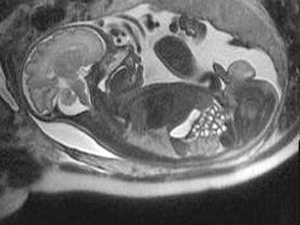

Рассмотрим несколько примеров МРТ-исследования плода.

На рисунке - тазовое предлежание плода, 26 недель. Нормальная анатомия головного мозга

На рисунке - плод, 38 недель. Структурные изменения головного мозга плода не выявлены. Определяется однократное обвитие пуповиной

На рисунке - плод, 39 недель. Двукратное обвитие пуповиной

На рисунке - плод, 34 недели. Головное предлежание, гипоплазия мозжечка

Диагностика мальформаций мозолистого тела по данным УЗИ часто представляет сложности. При этом результаты МРТ-исследования уже на 20 неделе гестации сравнимы с данными МРТ в постнатальный период.

На рисунке - плод, 29 недель. Агенезия мозолистого тела. Асимметричная гидроцефалия

МРТ плода позволяет диагностировать такие нарушения нейрональной миграции, как лисэнцефалия, гетеротопия, шизэнцефалия, мало доступные для диагностики при других методах исследования.

На рисунке - плод, 32 недели; поперечное положение плода. Шизэнцефалия